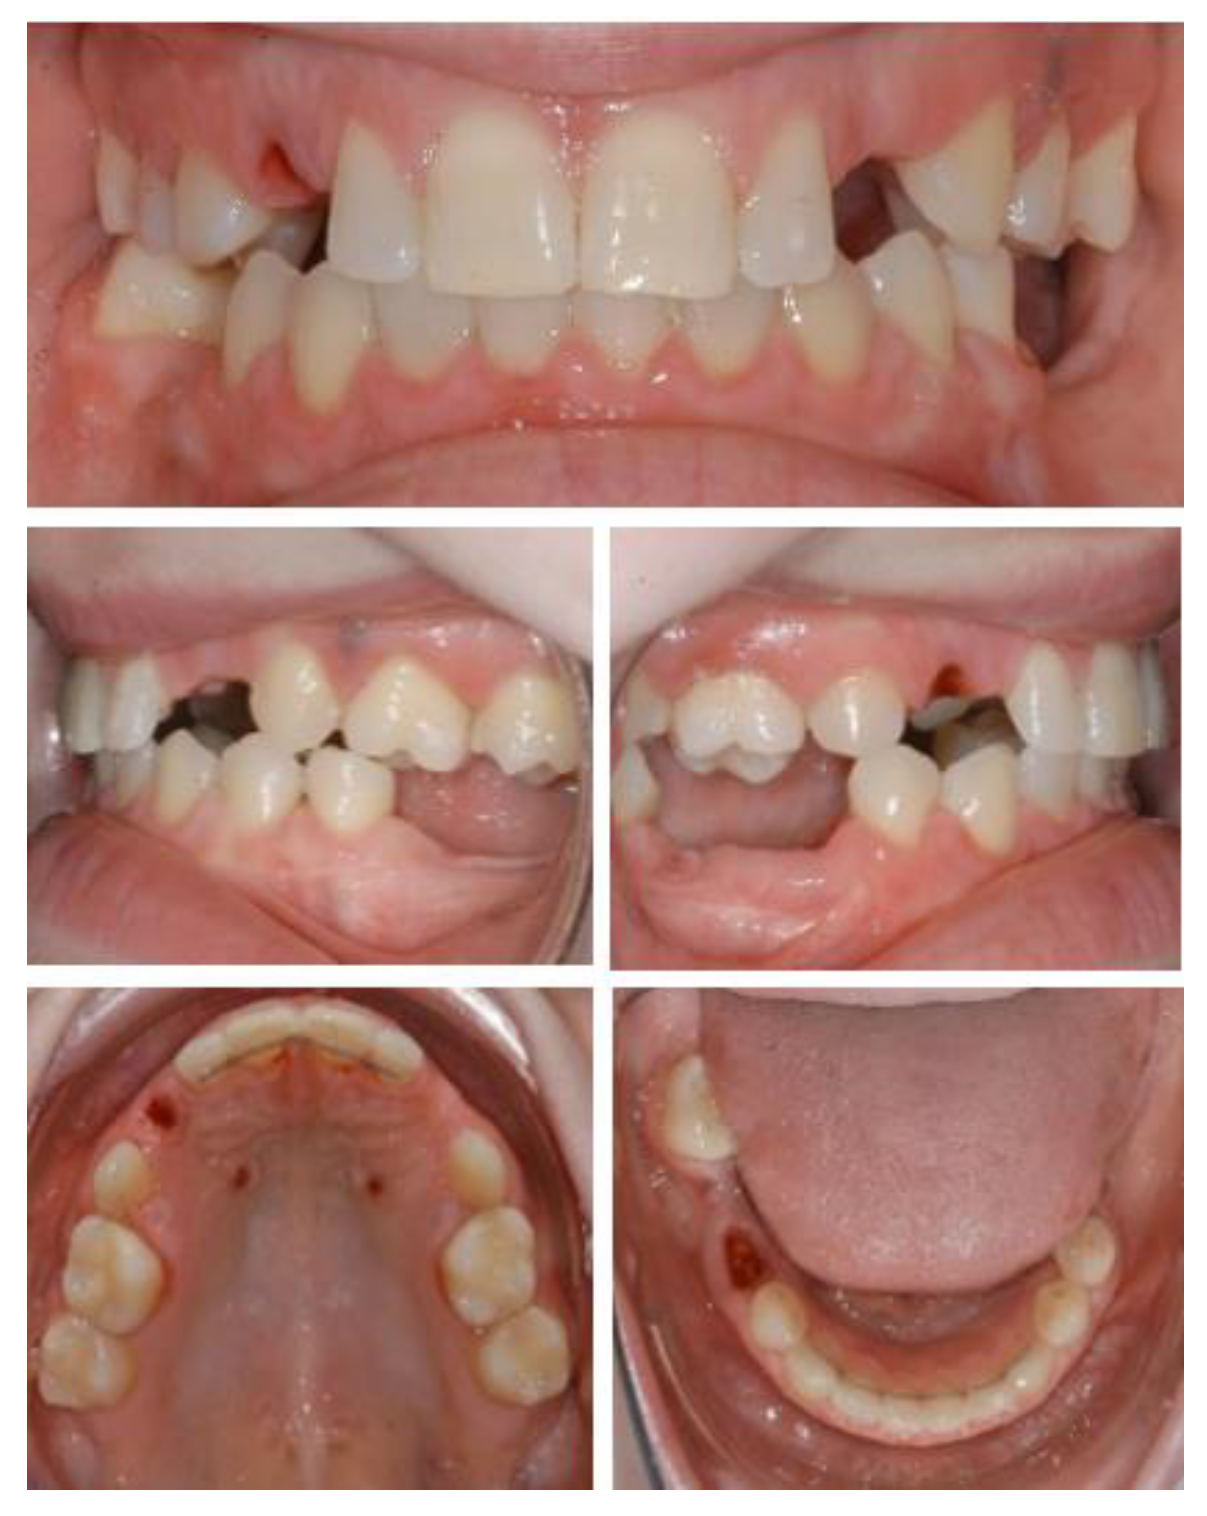

2.2. Case 2